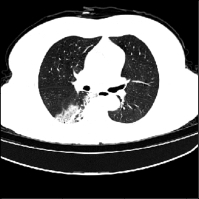

Recent studies indicate that detecting radiographic patterns on CT scans can yield high sensitivity and specificity for COVID-19 localization. In this paper, we investigate the appropriateness of deep learning models transferability, for semantic segmentation of pneumonia-infected areas in CT images. Transfer learning allows for the fast initialization/ reutilization of detection models, given that large volumes of training are not available. Our work explores the efficacy of using pre-trained U-Net architectures, on a specific CT data set, for identifying Covid-19 side-effects over images from different datasets. Experimental results indicate improvement in the segmentation accuracy of identifying COVID-19 infected regions.